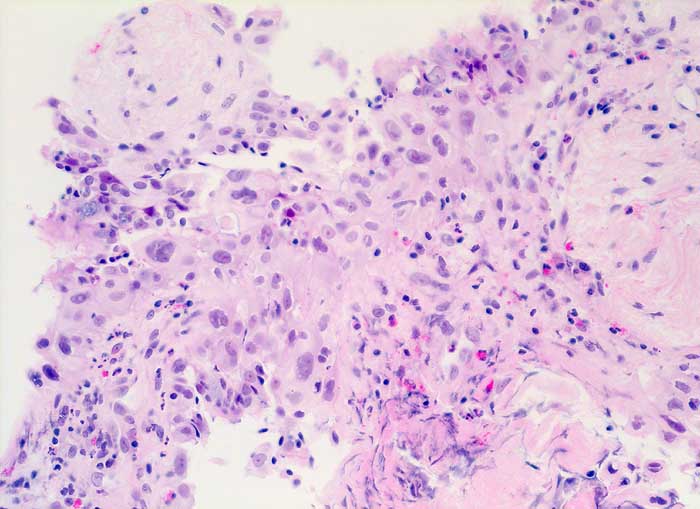

Nach Strahlentherapie eines mediastinalen Tumors oder eines Bronchuskarzinoms zeigen Bronchial- und Alveolarepithel ähnliche Kernveränderungen wie nach Zytostatikatherapie. Die Flimmerzellen haben unterschiedlich stark vergrösserte oft hyperchromatische und entrundete Kerne, sowie fragiles Zytoplasma. Der Nachweis von Flimmerhaaren und die erhaltene Kern-Zytoplasmarelation sprechen für reaktiv veränderte Bronchialepithelien.